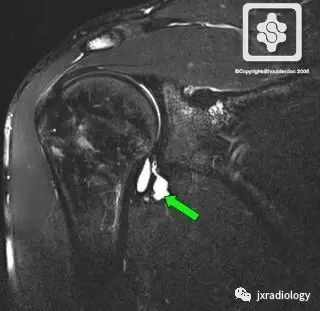

MRI is the investigation of choice, demonstrating atrophy +/- fatty infiltration in the teres minor and/or deltoid muscle. Literature review has shown varying proportions of deltoid and teres minor involvement.

MRI是首选的检查,表现为小圆肌和/或三角肌的萎缩+/-脂肪浸润。文献综述显示不同程度的三角肌和小圆肌的不同程度的受累。

MR Arthrogram showing a typical inferior paralabral cyst associated with a labral tear, causing QSS